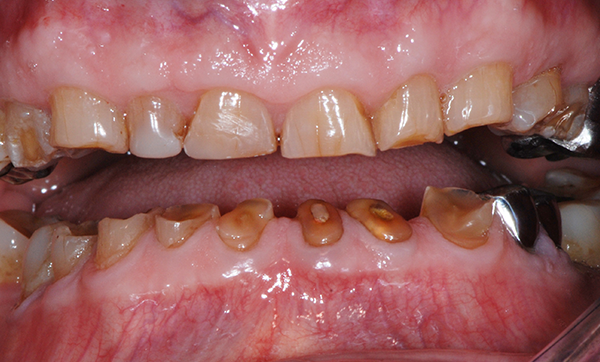

Bon nombre de praticiens considèrent le bruxisme uniquement au travers de l’effet inesthétique des attritions antérieures et du risque pour les thérapeutiques restauratrices ou prothétiques envisagées. Or, il existe un continuum permanent entre physiologie et pathologie. Outre les fonctions essentielles de mastication, ventilation et maintien de la posture, une autre fonction essentielle est à prendre en compte. Il s’agit de la fonction de décharge du stress par les parafonctions orales, en particulier par le biais du grincement et/ou du serrement des dents.